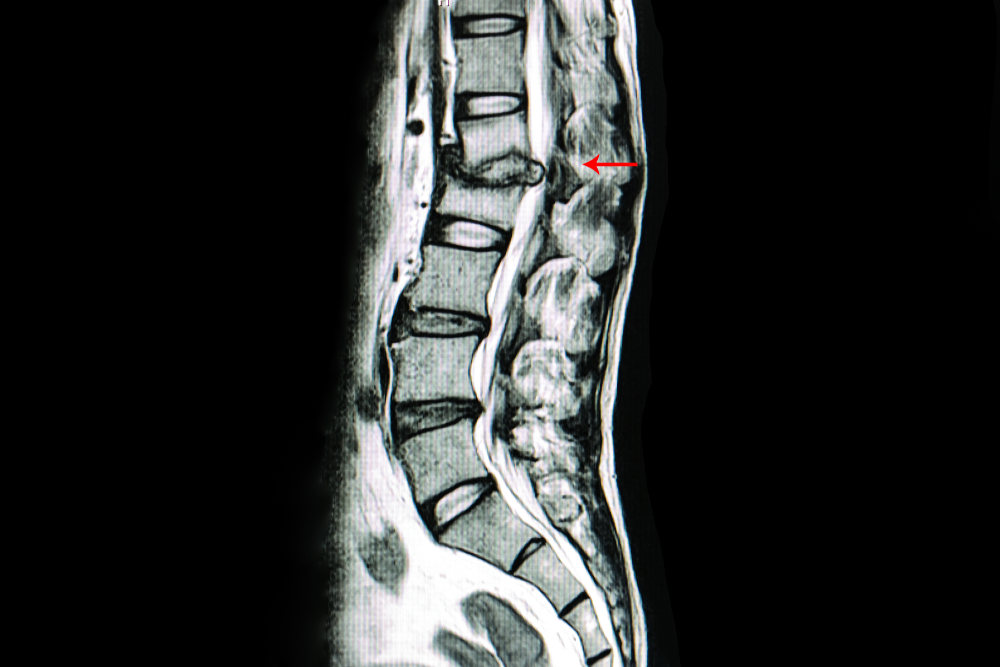

Pri osebah z dolgotrajnimi bolečinami v hrbtu in sistemskimi znaki okužbe, se opravijo krvni testi, kjer se pogosto zaznajo povišane vrednosti vnetnih markerjev (CRP). Ključno vlogo ima tudi slikanje z MR, saj omogoča natančno vizualizacijo sprememb v vretencih in medvretenčnih diskih že v zgodnji fazi bolezni. V določenih primerih se specialist odloči tudi za biopsijo ali hemokulturo, da se natančno določi povzročitelj okužbe.

Začetno stanje: Pacientka je poročala o močnih, stalnih bolečinah v ledvenem delu hrbtenice, kot tudi drugod po telesu, ki so se dodatno stopnjevale ob gibanju. Že dalj časa jo spremlja občutek izčrpanosti. Pred prihodom na diagnostično terapijo je izvedla MR slikanje in opravila pregled pri specialistu. Slikovna diagnostika je nakazala spondilodiscitis na nivoju L3-L4, hematološki markerji pa so potrdili prisotnost vnetja. Na dan diagnostične terapije je pacientka že bila deležna antibiotičnega zdravljenja.